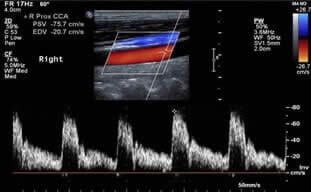

O Ultrassom Doppler (ou Duplex Scan) é um procedimento indolor que utiliza as imagens obtidas pela ultrassonografia, associadas à análise das ondas de som de alta frequência, que fazem uma análise do fluxo do sangue no interior dos vasos. Este exame fornece três tipos diferentes de informação ao médico. Primeiramente, ele constrói a imagem do vaso sanguíneo, idêntica a uma ultrassonografia comum. Em segundo, o Duplex avalia a velocidade e a direção do fluxo do sangue. Por último, o Duplex fornece uma imagem artificial colorida do fluxo sanguíneo, que facilita a identificação de pequenos vasos, expõe o sentido do fluxo do sangue, e pode mostrar áreas de turbulência deste fluxo, o que pode ser indicativo de alterações no vaso. Outra qualidade do Duplex é que este é um exame não invasivo, ou seja, não há necessidade de punções com agulhas ou ingestão de medicamentos.